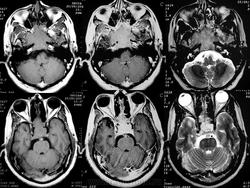

ГМ. Аденома гипофиза 1. +

Аденома гипофиза.